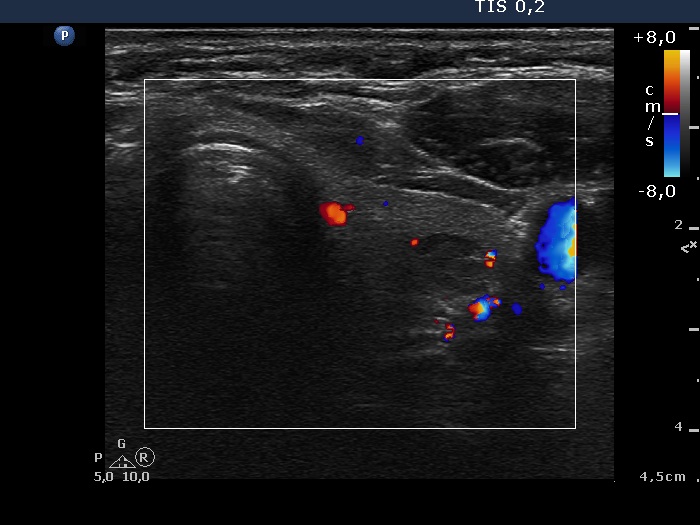

Upper part of the left lobe, transverse scan, color Doppler mode. The vascularization is not specific.